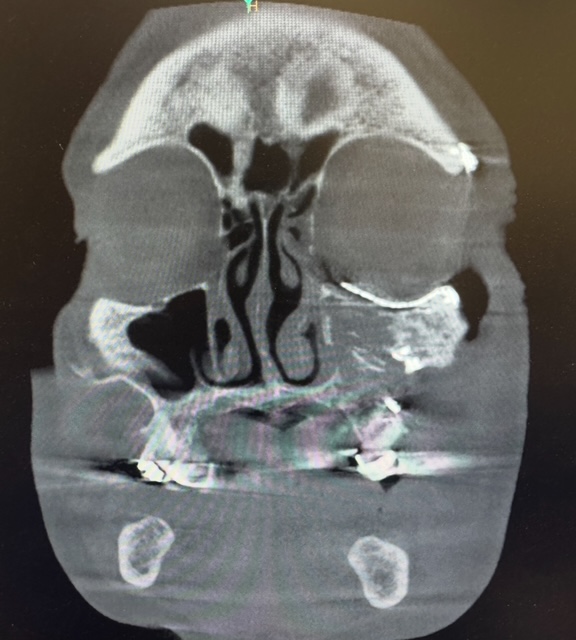

A young male patient presented to Hackensack University Medical Center after sustaining facial injuries subsequent to physical assault. As part of our NJ/NY hospital affiliations, Dr. Feuerstein and team were called to evaluate and treat the case. Imaging confirmed a left Zygomaticomaxillary Complex (ZMC) fracture and a left orbital floor fracture. These injuries affected midface projection, cheekbone position, and the structural support beneath the left eye. Without surgical repair, the patient risked:

Because of the complexity of the fractures, Dr. Feuerstein and team utilized advanced digital planning technology before entering the operating room. This included:

- 3D visual surgical planning

- Custom-designed plates for precise bone repositioning

- Cutting guides that act as templates for accurate reconstruction

The Left ZMC fracture required meticulous repositioning of displaced bone segments. Using multiple surgical approaches to access the facial skeleton, the custom plates designed in the planning phase, secured the cheekbone into its correct anatomical location.